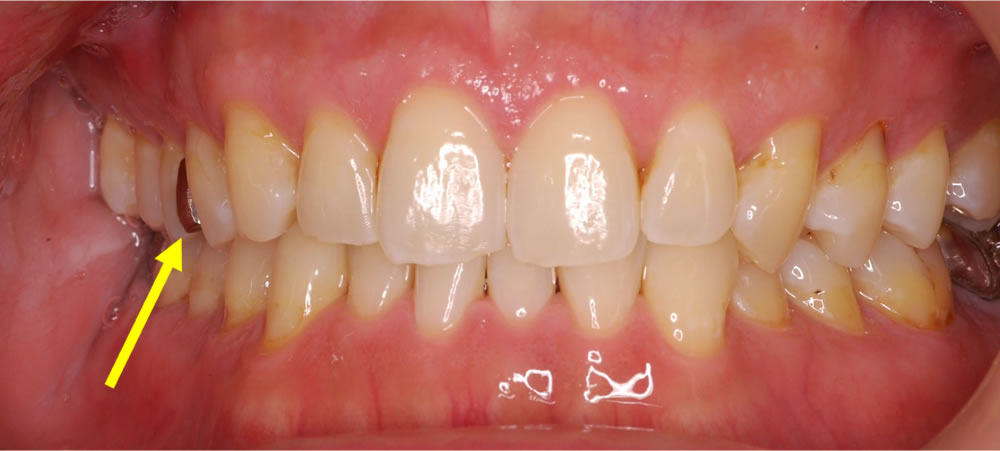

ジルコニアセラミックを用いて銀歯を白い歯にした審美症例

部分的に入った保険の銀歯を外して、ジルコニアセラミックのかぶせ物で見た目を改善した症例をご紹介します。(▼画像はクリックで拡大します)

こちらの患者さまは、過去に治療した右上奥歯の銀歯(黄色い矢印)の見た目が気になるとのことで来院されました。

噛む面と右の側面から見るとこのようになっています。患者さまと相談した結果、こちらの銀歯を取り除き、白い歯(ジルコニアセラミック)を被せて見た目を改善する治療計画を立てました。